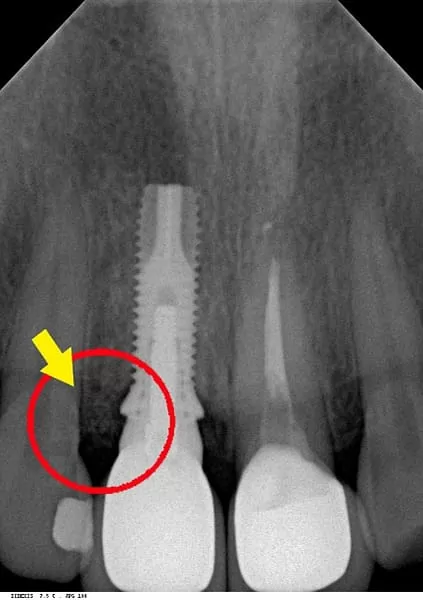

當天立即植牙,外側約5x7mm的骨缺損。缺損處醫師早再事前已經告訴我要實施 骨再生手術,充填骨粉後使用再生膜覆蓋並縫合傷口。治療後醫師讓我看手術中拍攝的照片,順便解說治療步驟,照片好嚇人喔!

醫師說比較最初與植牙後的X片,可見到當初不僅完整保留原來的骨質,並且再生手術引出更多的骨質,如此牙齦才能塑型到對稱、漂亮。我覺得很幸運可以來這邊將牙齒恢復美觀,從此可以擺脫"掉門牙"的惡夢,真的非常感謝敦南麗緻牙醫診所。